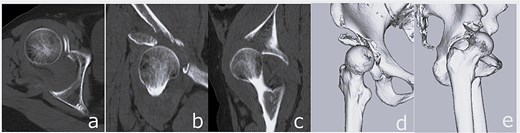

Surgery was performed via a posterior approach. The femoral head fragment avulsed at the ligamentum teres was found incarcerated within the acetabulum. Although fractures of the AIIS and anterior wall were identified, sufficient acetabular coverage and stable press-fit fixation of a cementless cup were achieved without additional internal fixation. A dual mobility cup (DMC) and a cementless femoral stem were implanted (Fig. 4).

Immediate postoperative anteroposterior (a) and lateral (b) radiographs demonstrating stable placement of the total hip arthroplasty components.